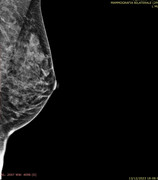

Dottor Catania,

secondo lei in questa mammografia di un anno fa erano presenti microcalcificazioni? Ingrandendo mi sembra di vedere in alto dei puntini...ma mi sa che li vedo perché li voglio vedere.. nella speranza che mi dicano che già c'erano e che non devo rifare tra 6 mesi un'altra mammografia...

Grazie

Ciarlina78

intendo questi puntini che vedo...